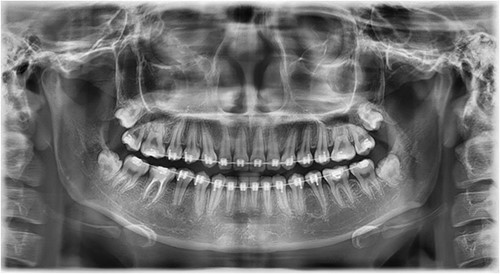

A Neumann full-thickness buccal flap was utilized to remove these during the course of orthodontic treatment. The shortcoming of the buccal surgical removal approach is that although it is better for visualization, it poses a high risk of trauma to the adjacent teeth or nerves [4, 5]. As the premolar was being removed on the right side, there was a fracture of the root apex (Fig. 2). On the left side, the premolar bud could be removed without any trauma to the adjacent tooth roots. After months of follow-up, there was normal bone formation, and no other symptoms were identified (Fig. 3).

Follow-up panoramic image 1-year after removal of the supernumerary premolars.